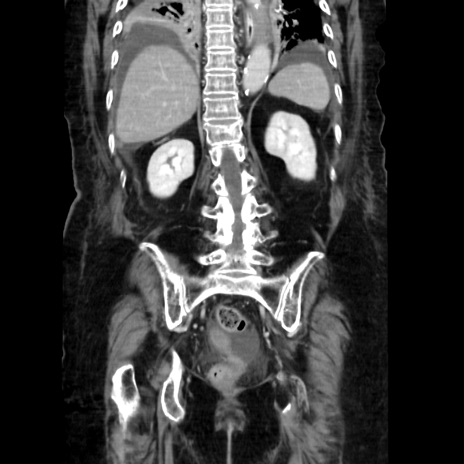

症例40(冠状断像)

【症例】90歳代女性

【主訴】腹痛・嘔吐

【現病歴】 食欲低下、嘔吐があり昨日他院受診。肺炎と診断され入院となる。入院後より腹部全体に圧痛あり。胃管留置され経過みていたが、症状持続するため、

当院転院となる。

【既往歴】胸椎圧迫骨折、胆石症

【身体所見】腹部:中央に激痛あり、圧痛あり、反跳痛不明

【データ】WBC 17100、CRP 18.82

冠状断像